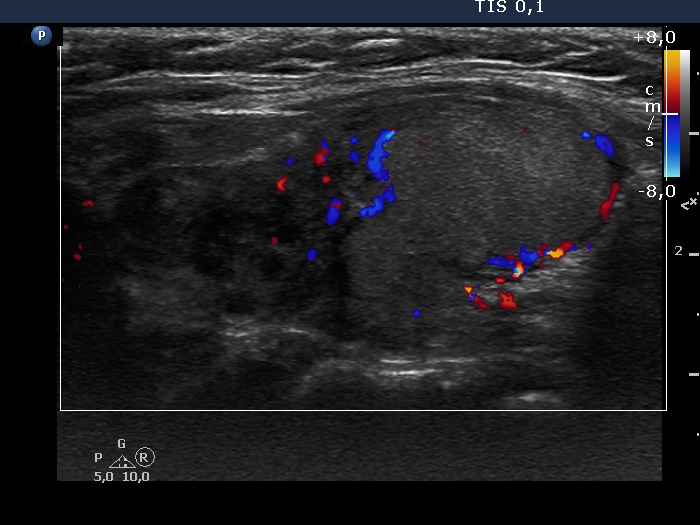

Left lobe, longitudinal scan, color Doppler mode. The lesion presents perinodular blood flow.